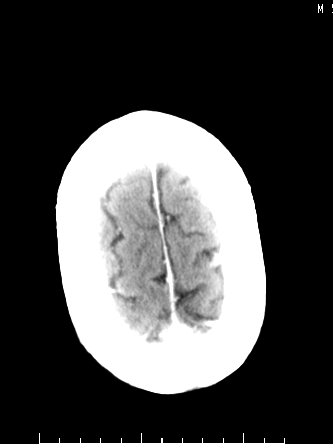

m/50,头昏头痛1月,近3天感觉左半肢体活动不利,自述半年前呈患肺tb,腰穿脑脊液未见特殊改变。现做头颅ct请大家会诊。

ct值?是囊变?梗塞软化灶形成

考虑颅内感染性病变:结核可能性大。

结核性脑膜炎,结核瘤,梗塞灶三症并存,提示颅内结核感染可能性大。

感染性病变;脑干脓肿(脓肿壁形成期),基底节及内囊(脑炎期)。顺便问一句,该病人是不是抵抗力很差,有没有糖尿病。

右侧基底节区缺血性脑梗塞.脑干区考虑结核.

可考虑结核,患者水肿范围大,囊性病灶边缘密度较高,不考虑胶质母细胞瘤